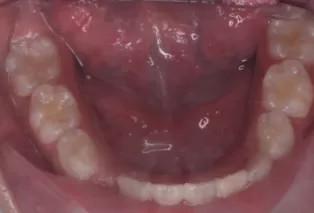

Intraoral photos